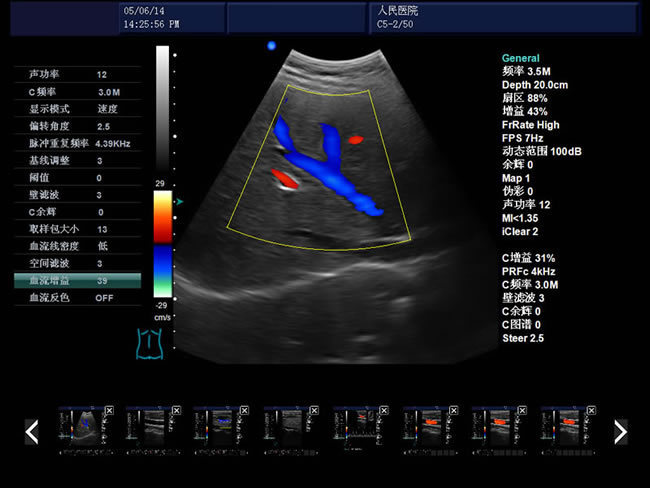

【D模式】--多普勒模式利用多普勒效应来检测血流速度和方向,根据血流向探头靠近或远离,显示不同的颜色,通常红色表示向探头靠近,蓝色表示远离。

彩色多普勒能清晰显示血流分布,频谱多普勒能定量测量血流速度。临床应用包括了心脏瓣膜功能评估、血管狭窄检测、血栓诊断和器官血供评估。而且彩色多普勒已成为了现代超声检查的标准配置。